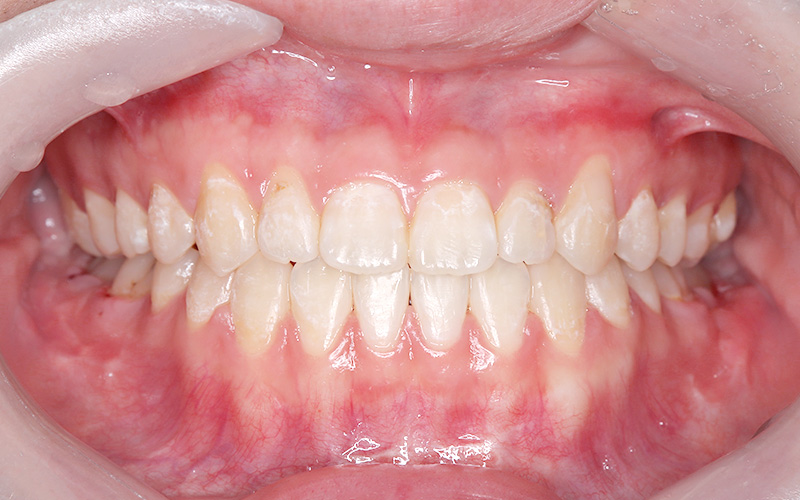

2上顎前突

主訴:口元が出ている(患者年齢:23歳5か月)

診断名:骨格性上顎前突症

治療に用いた主な装置:マルチブラケット装置、歯科矯正用アンカースクリュー

抜歯部位:上顎両側第一小臼歯、下顎右側第一小臼歯

治療期間:2年7か月

治療費概算およびリスク副作用:当科で設定している治療費に準じ、リスク副作用についても日本矯正歯科学会Hp掲載内容を説明(上記参照)

初診時